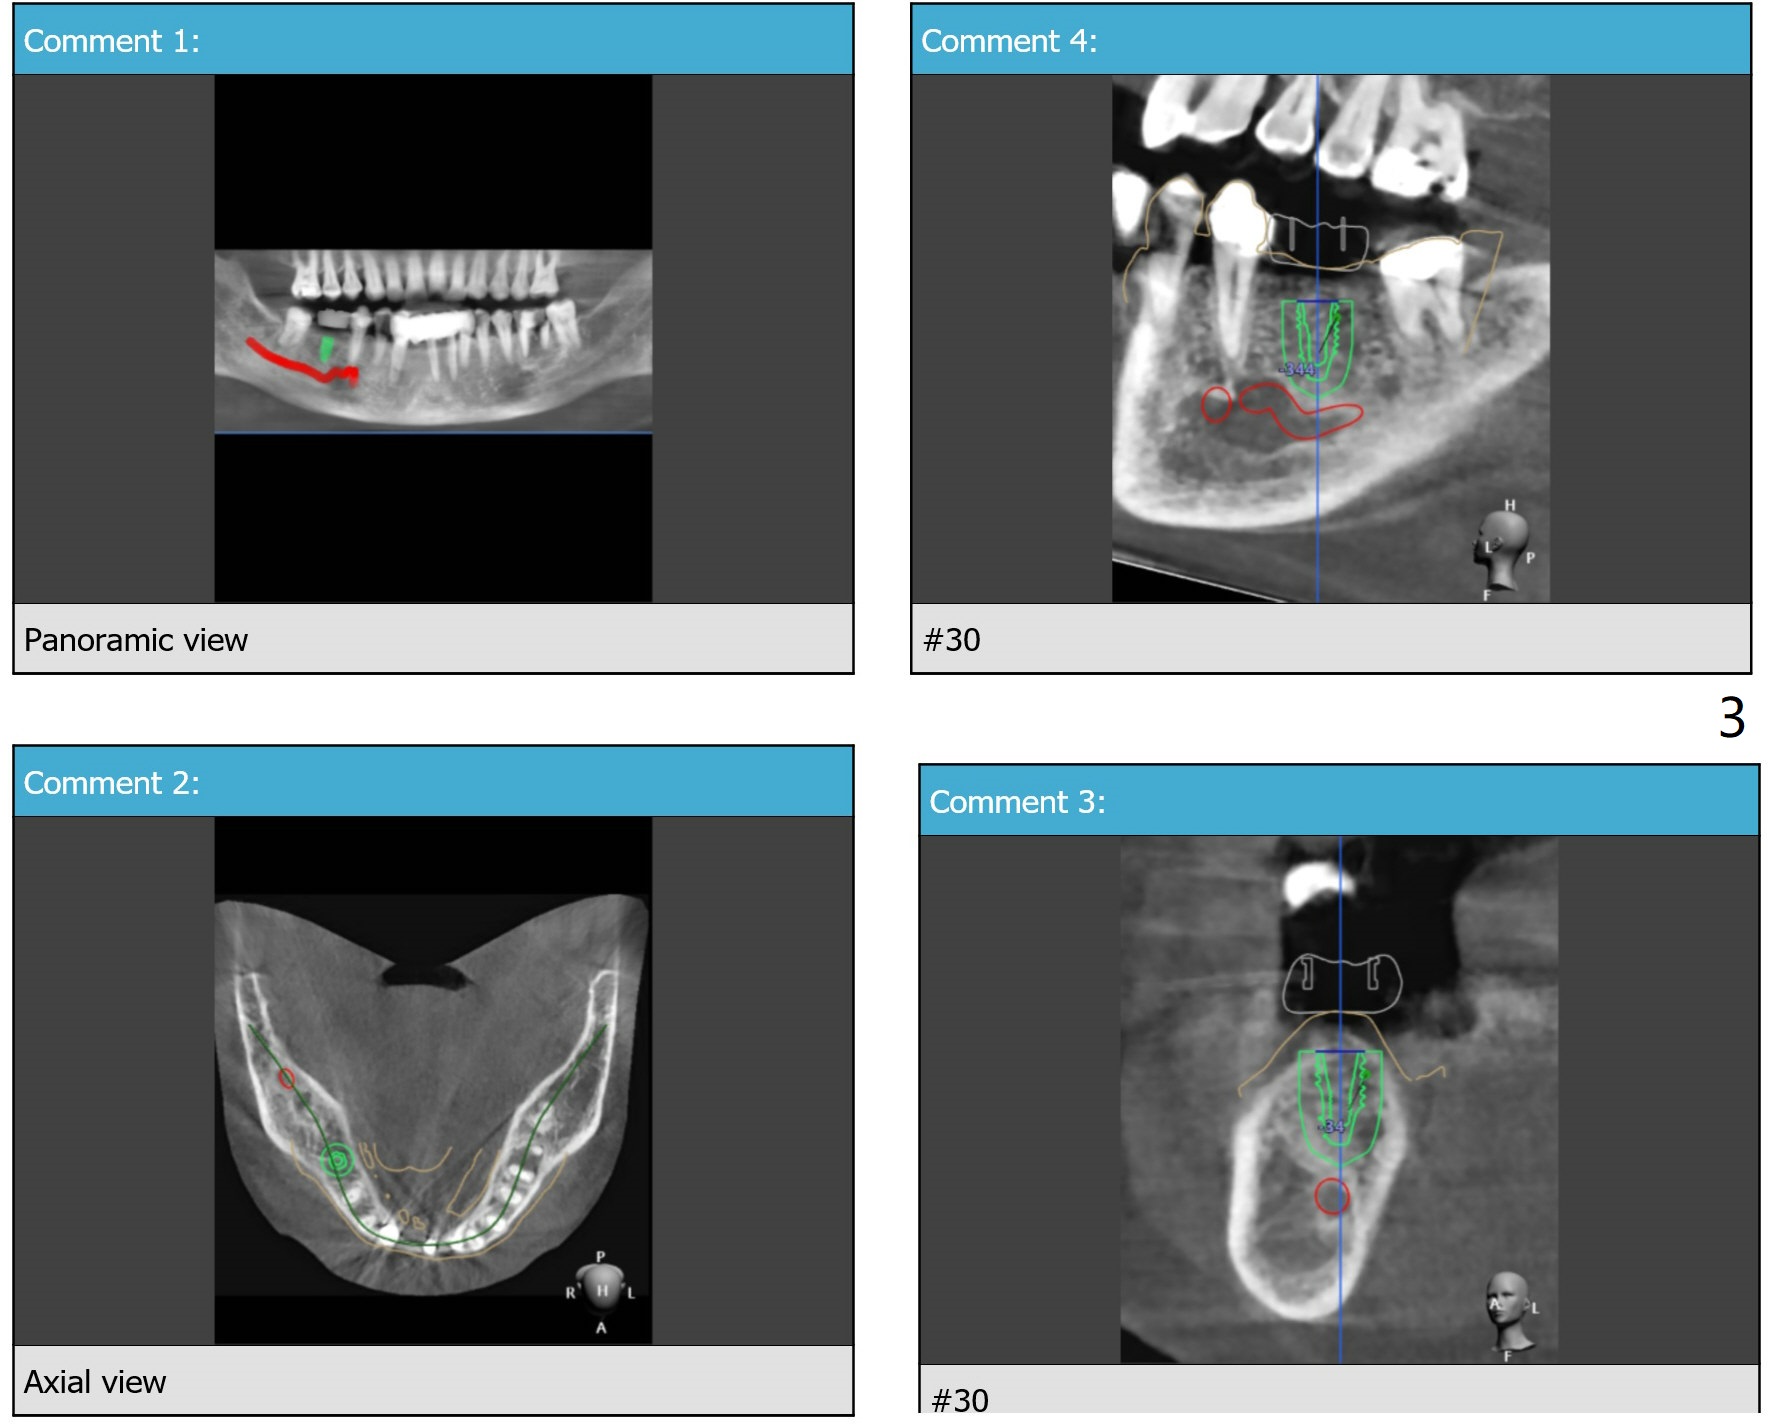

Distal Stop

The surgical guide for #30 will rest on the un-restorable tooth #31 as a distal stop. Following implant placement, the tooth #31 will be extracted with bone graft or plug in case of need of an implant in the future, although the tooth #2 is missing.